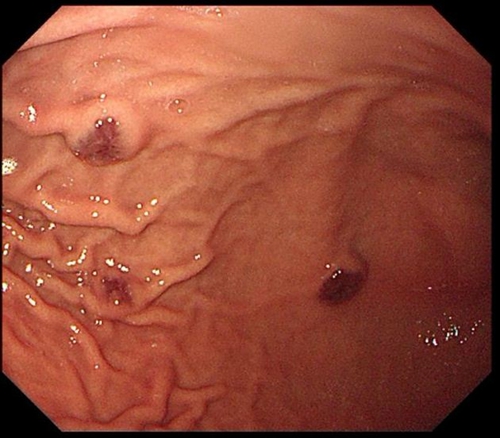

為了進一步查找病因,兒童消化內(nèi)科醫(yī)生決定利用“胃鏡+結(jié)腸鏡+膠囊內(nèi)鏡”三鏡聯(lián)合的方式進行檢查。檢查結(jié)果觸目驚心!

浩浩的胃、小腸及結(jié)腸內(nèi)有多發(fā)藍色大皰樣隆起,大大小小的有20多個,就好像在胃腸內(nèi)灑落了許多藍莓。尤其是小腸病變尤其明顯,最大顆幾乎堵塞了腸腔的一半。

兒童消化內(nèi)科急請血管瘤診療??茖<視\,結(jié)合既往病史,最終診斷為“藍色橡皮皰痣綜合征”。這些藍色大皰樣隆起其實是消化道靜脈瘤,間斷有靜脈瘤破裂出血,浩浩的重度貧血正是由于本病引起的長期消化道慢性出血所致。至此,困擾浩浩一家長達2年之久的反復(fù)貧血之謎得以解開。